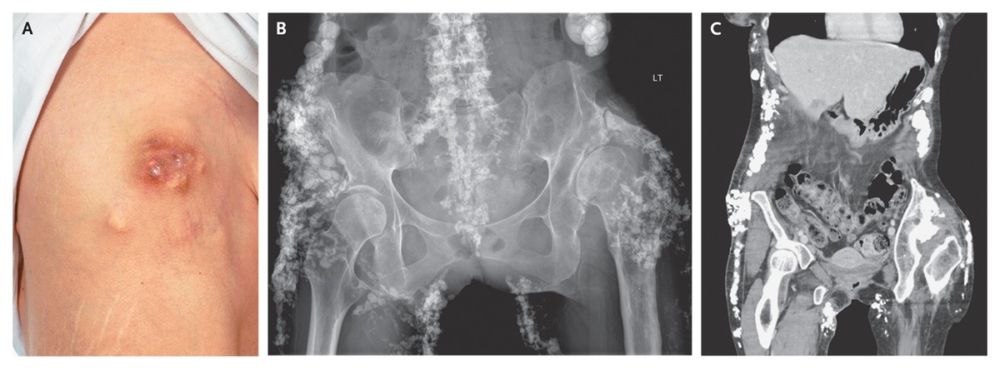

A 41-year-old woman received a diagnosis in 2000 of an overlap syndrome, with limited systemic sclerosis and dermatomyositis. Subcutaneous hard lumps developed over her buttocks and elbows in 2001 and progressed clinically (shown on the inferior axillary area of the right chest wall in Panel A) and radiographically (Panels B and C).

The biggest lesions were subsequently excised, but they reappeared within 1 year after surgery. Histologic examination revealed calcified deposits in subcutaneous fibrofatty tissue, findings consistent with a diagnosis of calcinosis cutis.